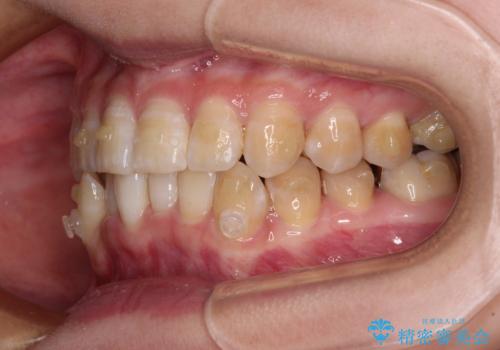

- 下顎の八重歯を気にして来院された患者様です。

マウスピース矯正でもワイヤー矯正でも対応可能であり、マウスピースによる治療を希望されたため、インビザラインを用いることとしました。

下顎前歯にデコボコが集中していたため、顎間ゴムによる後方移動とIPR(歯と歯の間を削ること)により歯列を整えることとしました。

下顎前歯のデコボコが集中しており、奥歯の咬み合わせは、上顎に対して下顎が前方位にある状態でした。下顎の歯列を後方へ移動させる治療はインビザラインの得意とするところですので、1年程度で無事に治療を終えることができました。